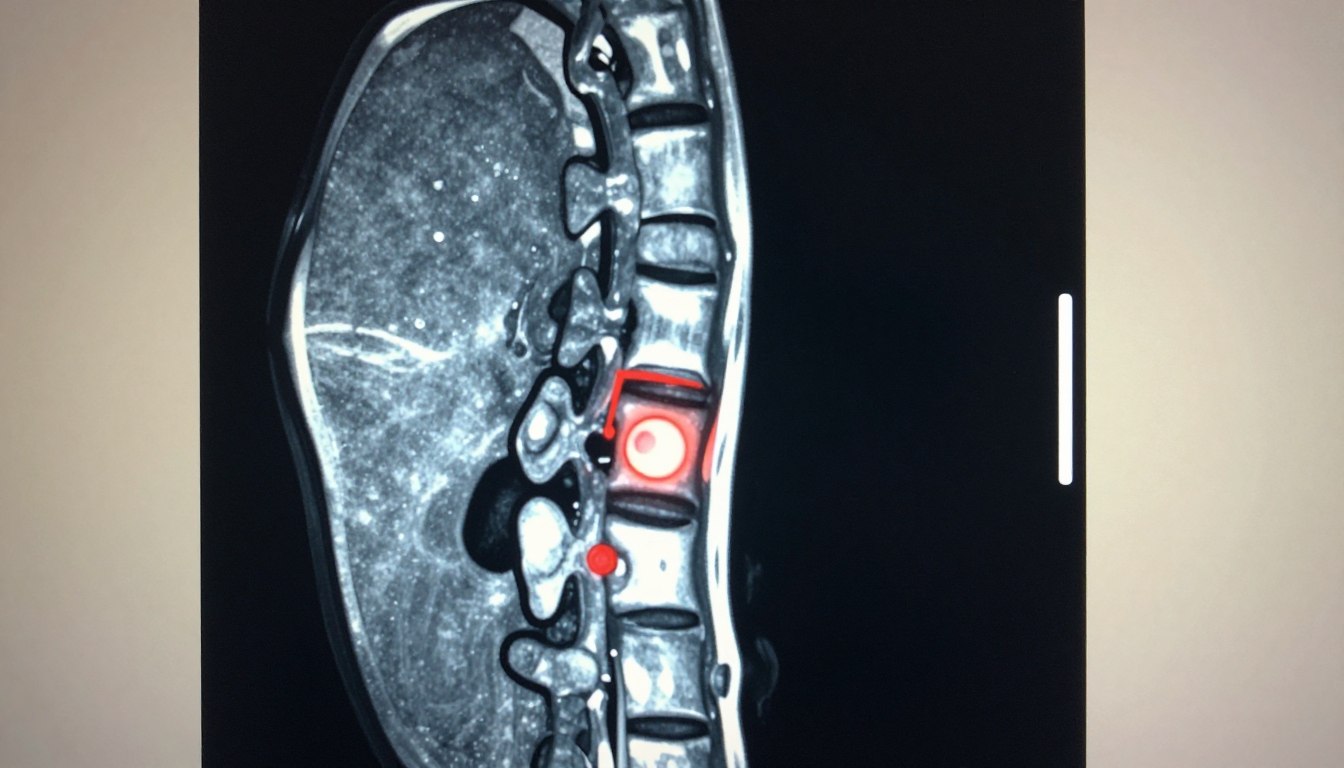

Czy lekarz rodzinny może wystawić skierowanie na tomograf – zasady skierowań i co warto wiedzieć

Czy pacjent może liczyć na skierowanie z POZ, gdy potrzebna jest tomografia? To pytanie często budzi wątpliwości: w praktyce NFZ d…